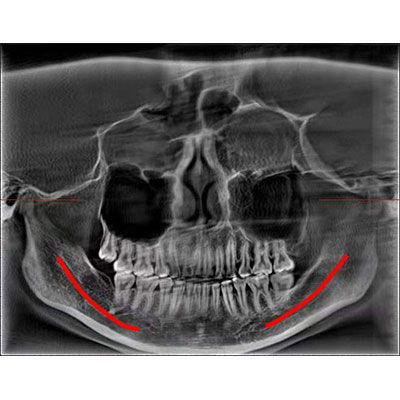

高清口腔全景影像

通过三维容积影像,提取高清口腔全景影像。

专有图像校正技术,去除金属伪影,提高图像分辨率。

Clinical picture

临床图片